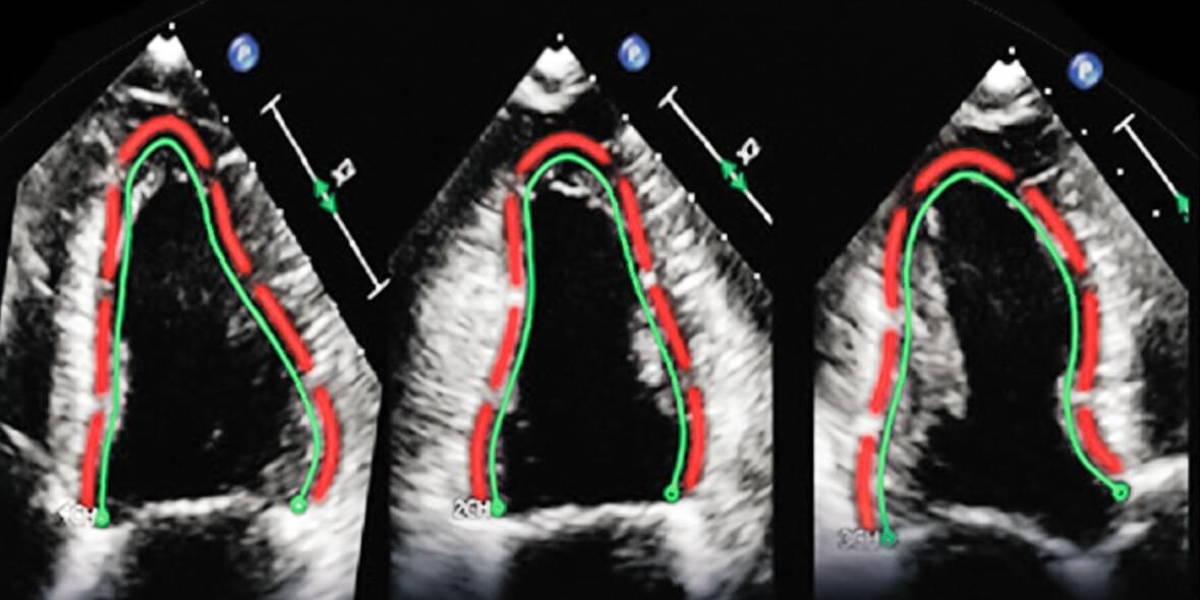

Headquartered in Munich, Germany, TomTec’s products and services promise to help clinicians to increase efficiency and diagnostic quality through automated and reproducible measurements. The acquisition will strengthen Philips’ leadership position in cardiac ultrasound, and support the company’s further expansion in other clinical areas, such as obstetrics and gynecology (OB/GYN).

Royal Dutch Philips has a large global installed base in ultrasound solutions and claims a broad and strong portfolio in areas such as real-time 3D imaging of the heart, quantification tools driven by Anatomical Intelligence, and ultra-mobile, portable ultrasound solutions. Philips’ ultrasound portfolio supports the effective and efficient delivery of care across a broad range of clinical specialties including radiology, cardiology, point-of-care and OB/GYN.

TomTec’s clinical applications, workflow solutions and R&D capabilities areto provide a highly complementary addition to Philips’ strengths in ultrasound image quality, 3D-imaging and transducer technology. The German company offers multi-modality and vendor-neutral diagnostic and analysis applications in cardiology, radiology and OB/GYN. Their software is used by more than 20,000 physicians and 600 health facilities worldwide to treat their patients daily.